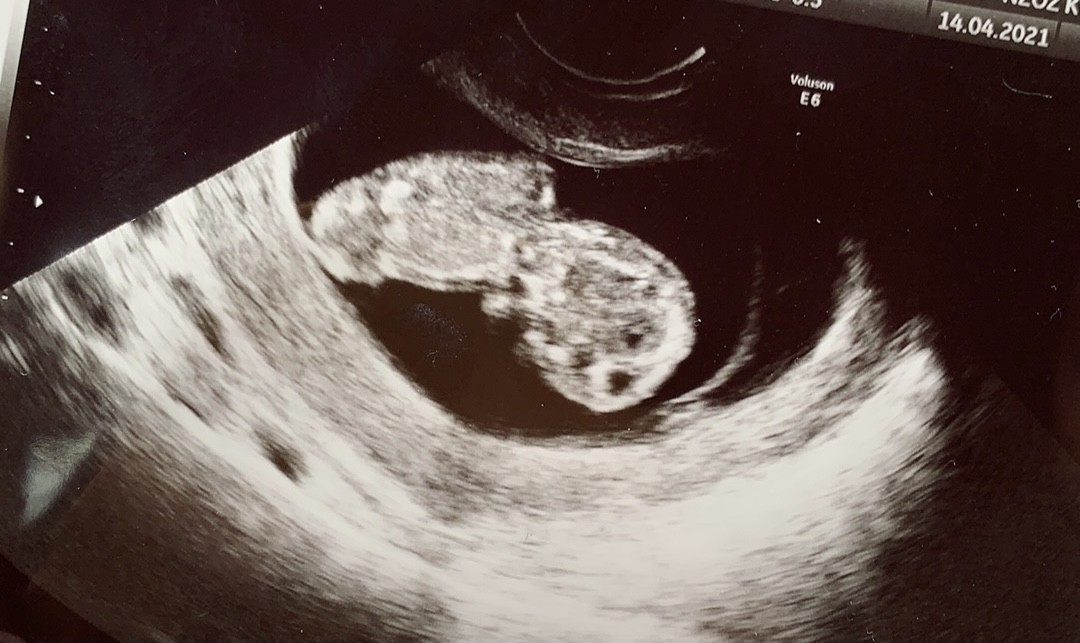

I znowu ja... Wczoraj miałam drugą wizytę. Aż mi łezka poleciała, jak zobaczyłam 4cm szczęścia 🍀❤️ Niesamowite uczucie🤰🏻

Załączniki

• A8FD46FB-0E78-40D1-8CE5-B085E7A8061A.jpeg

A8FD46FB-0E78-40D1-8CE5-B085E7A8061A.jpeg

135,6 KB · Wyświetleń: 129